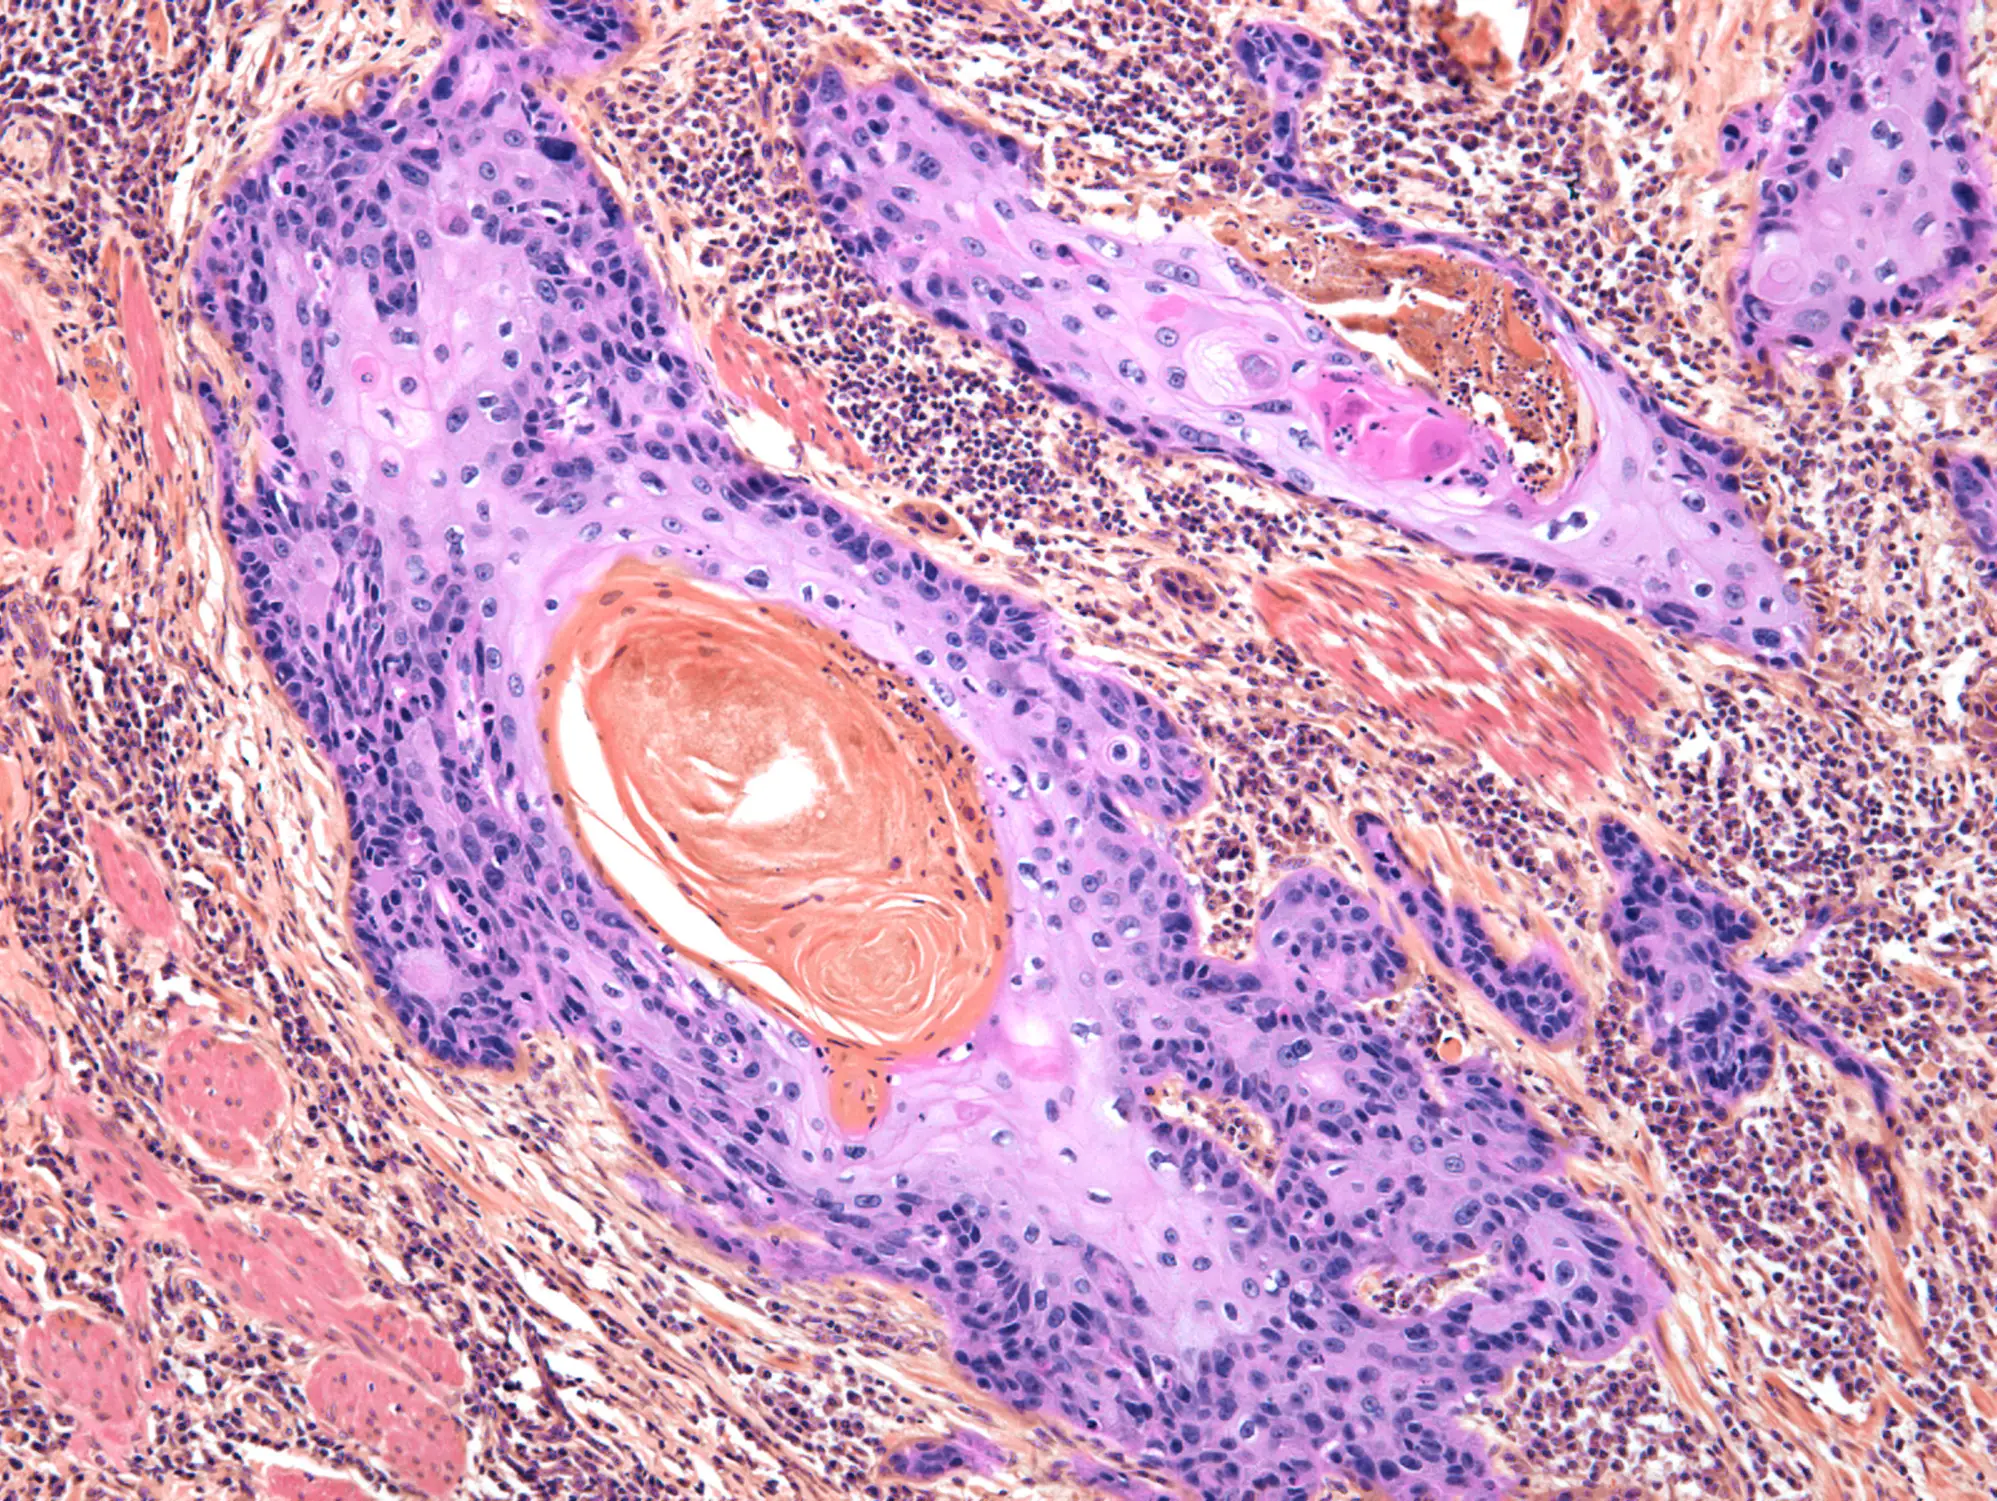

What is squamous cell carcinoma?

Squamous cell carcinoma occurs when the squamous cells in the skin have changes in their DNA, which instruct the cells to multiply quickly.

The cells then go on to invade and destroy healthy tissues and if untreated, can spread to other areas of the body.